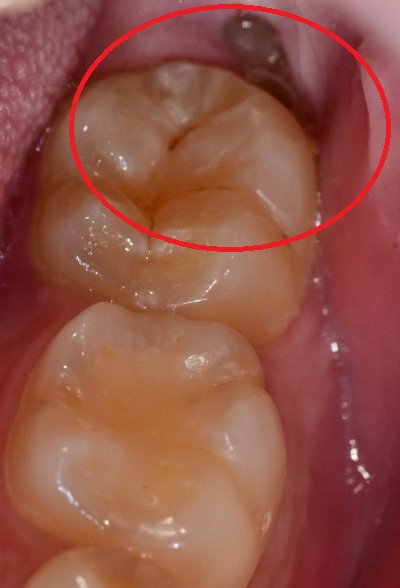

저 끝에 조금 나온 치아머리가 보이시나요?

평소에는 아무런 문제가 없었겠지만

우연히 음식물 잔사가 저 틈에 끼게 되고

잇몸이 붓게 되면 그 벌어진 틈으로

감염이 일어나 통증이 야기되는 것입니다.

보시는 바와 같이 저 부위를 평소에 양치를 꼼꼼하게 하는 건 쉽지 않습니다.